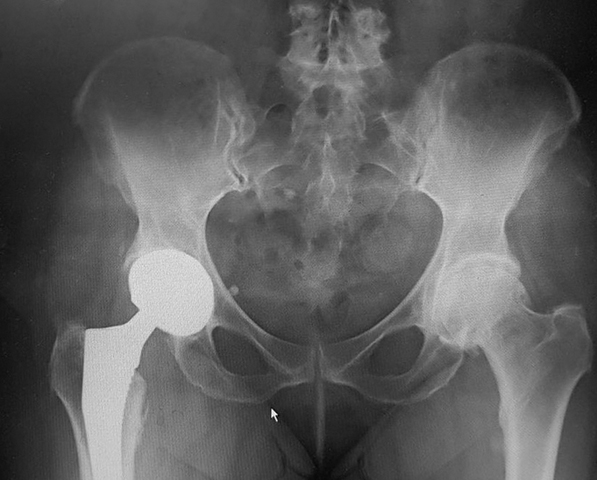

Iz lične foto-dokumentacije doc. dr Barjaktarovića:

Obostrana artroplastika kuka |

Postoje različite vrste veštačkih zglobova, ali se oni uglavnom dele na implantate koji se za kost vezuju posebnim koštanim cementom (cementna artroplastika), proteze koje se direktno postavljaju na kost, za koju se vezuju urastanjem (bescementna artroplastika), i hibridne artroplastike (kombinacija ove dve). Uzimajući u obzir i trajnost veštačkih zglobova, ali pre svega indikacije, kao i životnu dob i stanje koštano-mišićnih struktura individualnog pacijenta, uslovno bi se moglo reći da je cementna artroplastika uglavnom rezervisana za starije, a bescementna za mlađe osobe. Cementne endoproteze se ugrađuju osobama starijim od 75 godina, odnosno pacijentima sa krhkijom koštanom strukturom, i prisutnom osteopenijom ili osteoporozom. One, naime, obezbeđuju bržu i lakšu rehabilitaciju i vraćanje svakodnevnim životnim aktivnostima, zahvaljujući tome što se implantat brzo vezuje za kost uz pomoć polimera, takozvanog koštanog cementa (polimetil metakrilata). Nakon primene ove polimerske veze pri ugradnji veštačkog zgloba, pacijentu je dozvoljeno da se oslanja na operisanu nogu od samog početka vertikalizacije, te se on vrlo brzo oporavlja - već sutradan po operaciji spreman je na pun oslonac i može da hoda bez bola. Dr Barjaktarović dodaje da se cementne endoproteze najčešće koriste pri zameni zgloba kolena zato što je artroplastika kolena najučestalija u starijoj populaciji, za koju je poznato da je najpogođenija degenerativnim promenama koje oštećuju zglob kolena.

Iz lične foto-dokumentacije doc. dr Barjaktarovića:

Obostrana koksartroza |

Bescementna artroplastika primenjuje se kod ljudi mlađe životne dobi, ali i kod starijih osoba koje imaju očuvanu koštanu građu. Bescementni implantati, uglavnom izrađeni od metala (titanijuma i njegovih legura), direktno se postavljaju na kost jer su njihove površine takve izrade da omogućavaju punu osteointegraciju (urastanje i vezivanje kosti) - nekoliko meseci nakon operacije implantat i kost postaju jedinstvena celina. Dr Barjaktarović ističe da je za bescementnu artoplastiku neophodan preduslov postojanje odgovarajućeg kvaliteta kosti, to jest zdrava gustina i građa kosti, da bi ona iznela teret implantata i podržala spoj između kosti i metala.

U Srbiji je, prema istim starosnim kriterijumima, i zakonski predviđeno (od strane Republičkog fonda za zdravstveno osiguranje) da se pacijentima starosti do 65 godina implantiraju bescementni veštački kukovi, pacijentima starosti od 65 do 75 godina takozvani hibridni implantati (jedna komponenta endoproteze se vezuje cementom, druga bescementno), a starijima od 75 godina isključivo cementni implantati.